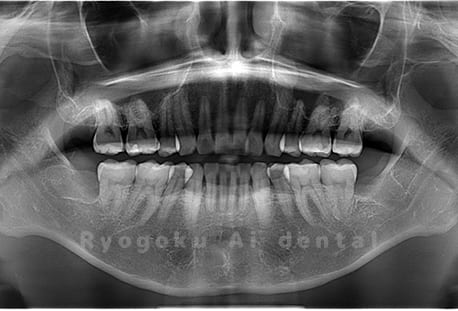

Case02

- 下顎の水平埋伏智歯

- 治療内容

- 下顎の水平埋伏智歯を抜歯

<リスク・副作用>

手術後は痛み、腫れ、痺れなどの副作用が生じる場合があります。